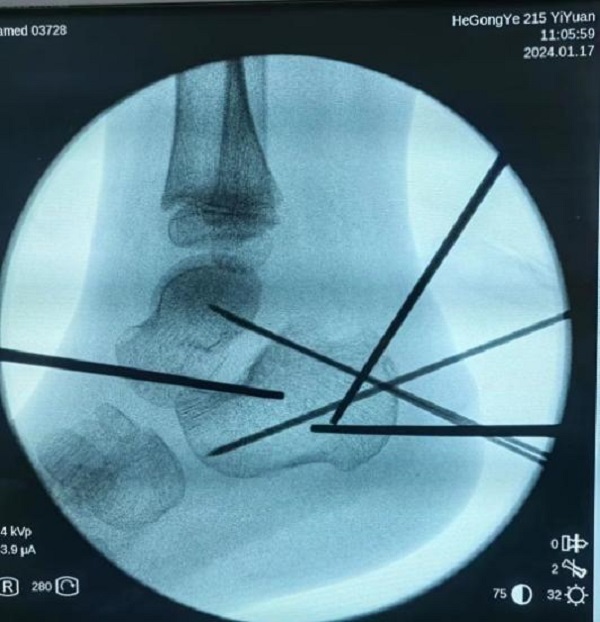

病情研判过程中,考虑到孩子年龄尚小,必须以最小的创伤完成治疗,用最快的速度让孩子恢复。宋强主任多频次组织团队阅片讨论,探究最佳诊疗方案。讨论认为,此例跟骨骨折涉及关节面,并且出现关节面塌陷,手术指征非常明确。在与家属充分沟通取得信任和支持后,宋强主任团队决定为小铎施行踝关节镜下微创手术治疗。考虑到儿童的病情进展较快,伤后第3天,手术便紧急开展。

手术过程中,关节镜从微小的窗口进入患儿体内探查,将病灶部位情形以最大视角、最佳角度呈现在监视画面中。关节镜直视下发现,关节面分离移位的程度远超影像资料提供的片面数据,手术的难度与复杂程度比预想的要大很多。在关节镜的辅助下,宋强主任团队专注谨慎,每一个步骤、每一次下刀都力争分毫无差,凭借多年累积的专业经验和技术水平,在约一个半小时的精细操作后,关节成功复位,手术精准且顺利的完成。

复位后,达到满意效果

关节面成功复位,创伤也很小